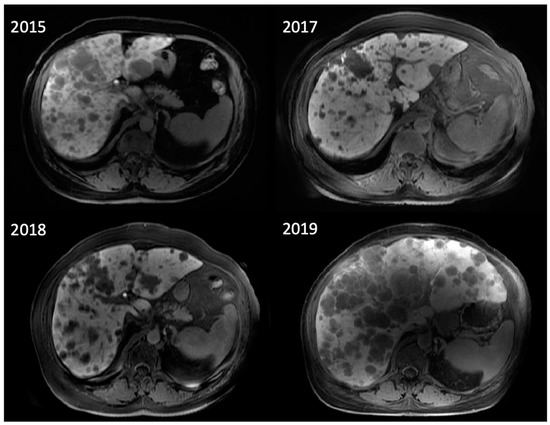

Figure 3.

A 73-year-old man with diffuse large B-cell lymphoma. Maximum intensity projection and axial fused FDG PET/CT pre- (above) and 28 days post- (below) CAR T-cell therapy demonstrating resolution of hypermetabolic adenopathy in the right lower neck consistent with complete metabolic response.

Figure 4.

A 70-year-old man with refractory diffuse large B-cell lymphoma. Maximum intensity projection and axial fused FDG PET/CT pre- (right) and 3 months post- (left) CAR T-cell therapy showing marked decrease in size and FDG uptake of right upper lobe lymphomatous mass invading the right chest wall (arrow). Slight increase in FDG uptake of left upper lobe pulmonary nodule (arrow), also suspicious for lymphoma.